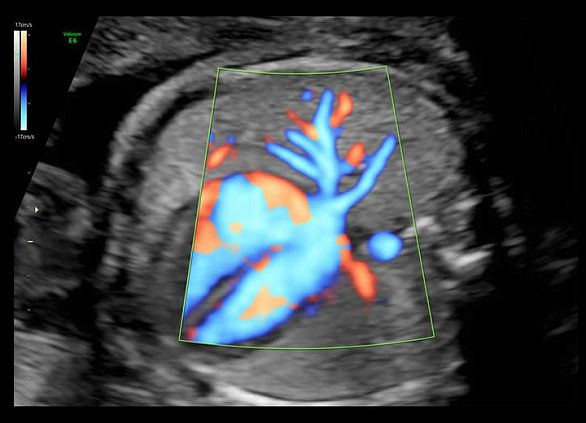

Клинические изображения

- Высокочувствительный допплер (HD-Flow).

УЗИ аппарат Voluson E6 гарантирует превосходное качество визуализации как 2D-режиме, так и при объемной реконструкции в 3D/4D режиме, а также при цветовом допплеровском картировании. Благодаря инновационным инструментам автоматизации и интуитивному интерфейсу пользователя достигается существенное сокращение времени исследований, упрощается труд врача, снижается утомляемость и повышается общая производительность и пропускная способность.

- Высокочувствительный допплер (HD-Flow).

УЗИ аппарат Voluson E6 гарантирует превосходное качество визуализации как 2D-режиме, так и при объемной реконструкции в 3D/4D режиме, а также при цветовом допплеровском картировании. Благодаря инновационным инструментам автоматизации и интуитивному интерфейсу пользователя достигается существенное сокращение времени исследований, упрощается труд врача, снижается утомляемость и повышается общая производительность и пропускная способность.